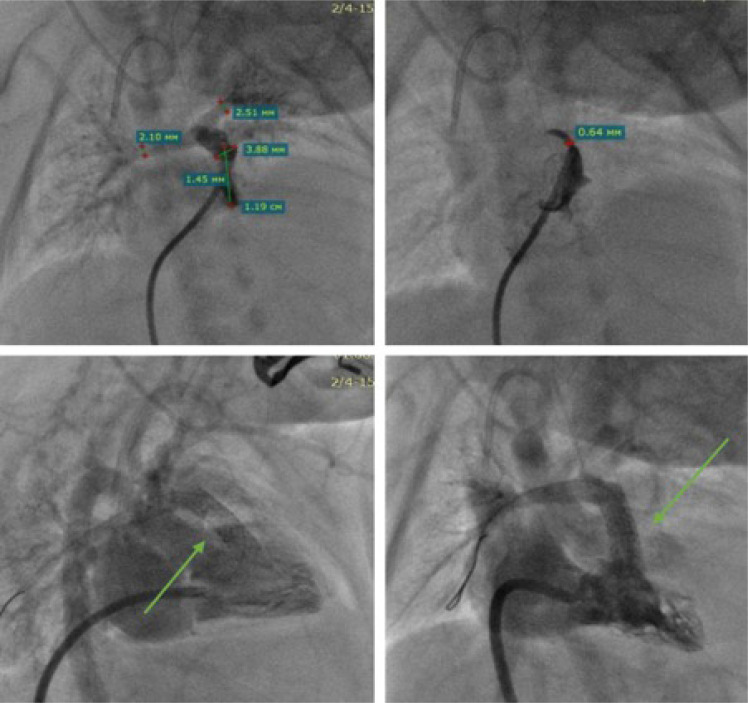

Methods: This prospective, randomized, two-center study included infants with tetralogy of Fallot who underwent surgery between June 2018 and 2022. The patients were divided into two groups - those who underwent stenting of the right ventricular outflow tract (stent group, n=21) and those who underwent modified Blalock-Taussig shunt placement (shunt group, n=21).

Results: In the stent group, a significantly greater increase in Nakata index was observed, with mean values rising from 104.2 to 208.6 mm2/m2, compared to an increase from 107.3 to 169.4 mm2/m2 in the shunt group (P<0.01). According to the mixed model analysis, the rate of growth of the right pulmonary artery in the stent group was 2.05*10-2 z score/day, which was 3.01 times greater than that in the shunt group (P<0.01). The rate of growth of the left pulmonary artery in the stent group was 2.3*10-2 z score/day, which was 1.47 times greater than that in the shunt group (P<0.01). In one patient (4.8%), after 76 days following the stenting of the RVOT, a severe infectious process with sepsis occurred, leading to a fatal outcome. Complete correction in the stent group involved transannular patch repair of the right ventricular outflow tract to the pulmonary artery in 12 patients (60%), while the same procedure was performed in 15 patients (71.4%) in the shunt group (P=0.52).

Conclusion: Stenting of the right ventricular outflow tract provides hemodynamic stabilization and symmetric growth of the pulmonary vascular bed compared to the formation of a modified Blalock-Taussig shunt.